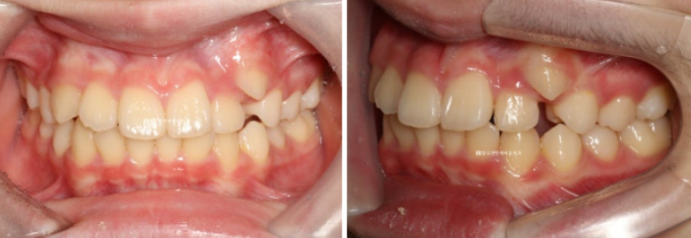

덧니가 있어서 내원한 학생입니다.

덧니를 고치고 싶어서 내원을 하였지만, 위 아래 중심선도 맞지 않는 것이 보입니다.

중심선은 덧니쪽으로 쏠려 있는 경우가 많고 덧니가 개선이 되면 중심선도 자연스레 맞아집니다.